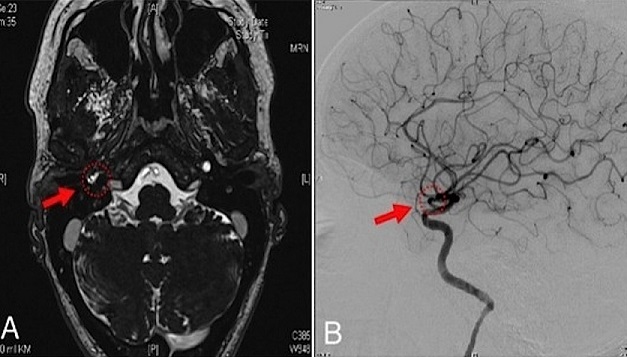

A massive bleeding from the right ear, the nose and from the mouth occurred in a 46-year-old female after ambulatory myringotomy was performed in order to treat symptoms mimicking a persisting middle ear effusion with conductive hearing loss. The patient was directly admitted to our intensive care unit. The bleeding continued until the blood pressure was lowered to normal and the patient was positioned in an upright position. Otoscopy showed a pulsatile bleeding through a perforation of the tympanic membrane. Endoscopy of the epipharynx showed fresh blood coming from the eustachian tube. MRI (Panel A) and angiography (Panel B) showed an aberrant internal carotid artery on the right side in the petrousal part with a thorn-like protrusion at the side of injury followed by a decreased vessel-diameter directly below the injury (Panel A, B). No coincidental aneurysm or vascularised tumor are found. Aberrant internal carotid artery in the middle ear is rare. Without prior diagnosis routine myringotomy can cause life-threatening situations. If a bluish-red formation behind the tympanic membrane is seen combined with the symptoms of pulsatile tinnitus and conductive hearing loss, a vascular malformation in the middle ear should be suspected and imaging of the temporal bone should precede any intervention. To prevent puncture of aberrant vessels in the middle ear, a paracentesis should in suspicious cases rather be performed with a sickle knife especially and not with a lancet.